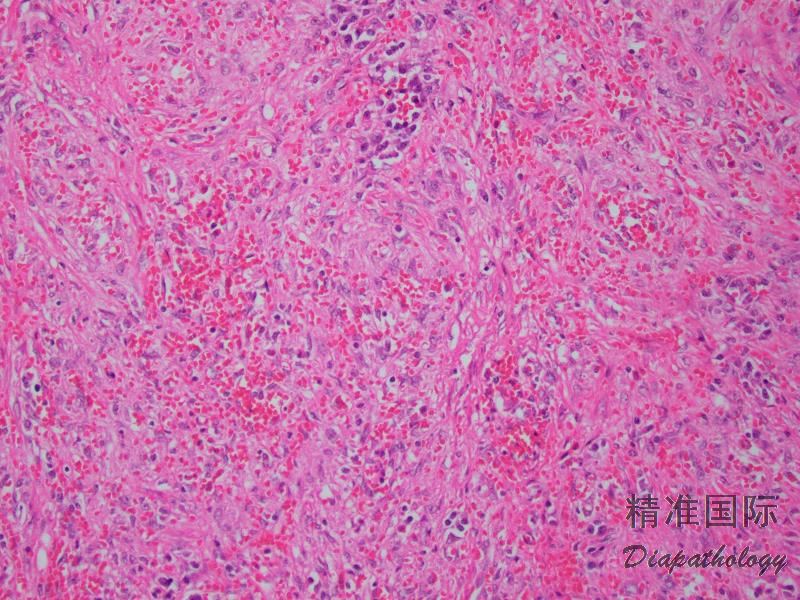

组织学上,IMT 由比例多少不等的梭形或多角形细胞、纤维/肌纤维母细胞以及淋巴浆细胞混合性组成,部分病例可见嗜酸性粒细胞和中性粒细胞浸润;

梭形细胞可见致密的席纹状或束状排列仅见少量的炎细胞浸润,亦可表现为广泛的炎性背景仅有少数梭形肿瘤细胞;

根据病变时限的长短,IMT 可显示一系列谱系的形态学改变包括相对温和和少细胞的硬化性病变至更富于细胞和伴有非典型性的病变,有时可以某种形态学为主,亦可同时出现在同一病变内;

核分裂象多少不等,但通常较少,罕见坏死;

具有较多神经节细胞样肿瘤细胞的 IMT 相对较可能显示侵袭性的生物学行为;